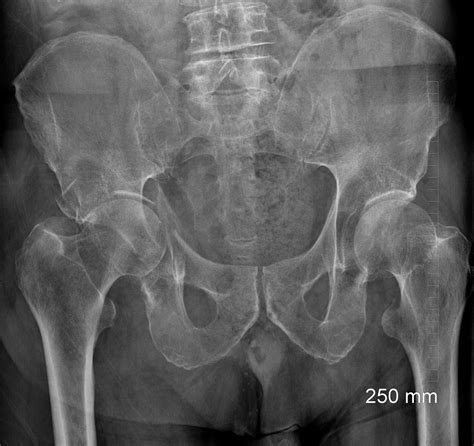

Hairline Fracture Hip Symptoms